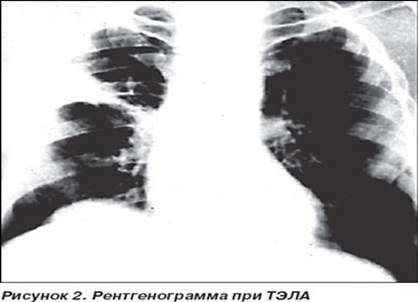

4). Рентгенографические признаки ТЭЛА малоспецифичны в первые сутки. Наиболее характерные симптомы острого легочного сердца: расширение верхней полой вены, расширение конуса легочной артерии, сглаживание талии сердца. Могут наблюдаться увеличение правых полостей сердца, выбухание дуги легочной артерии, отсутствие пульсации и расширение корня легкого, обеднение легочного рисунка в зоне разветвления тромбированного ствола легочной артерии (с-м Westermark, 1958), наличие клиновидной тени, высокое стояние купола диафрагмы и ограничение ее подвижности на стороне поражения (с-м Цвейфеля).